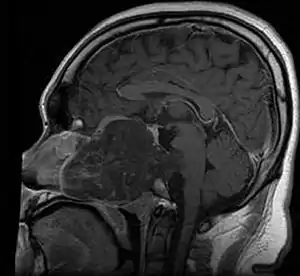

| MRI of extensive clival chordoma in 17-year-old male patient, axial view. Tumor in the nasopharynx extending from nasal cavity to brainstem posteriorly is clearly visible. | |

Chordomas can arise from bone in the skull base and anywhere along the spine. The two most common locations are cranially at the clivus and in the sacrum at the bottom of the spine.[2]